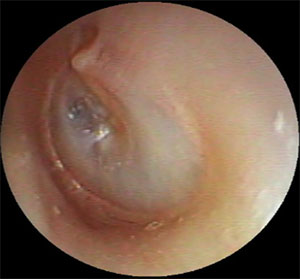

| 左外耳道炎 | ||

| 治療前 | 治療後 | |